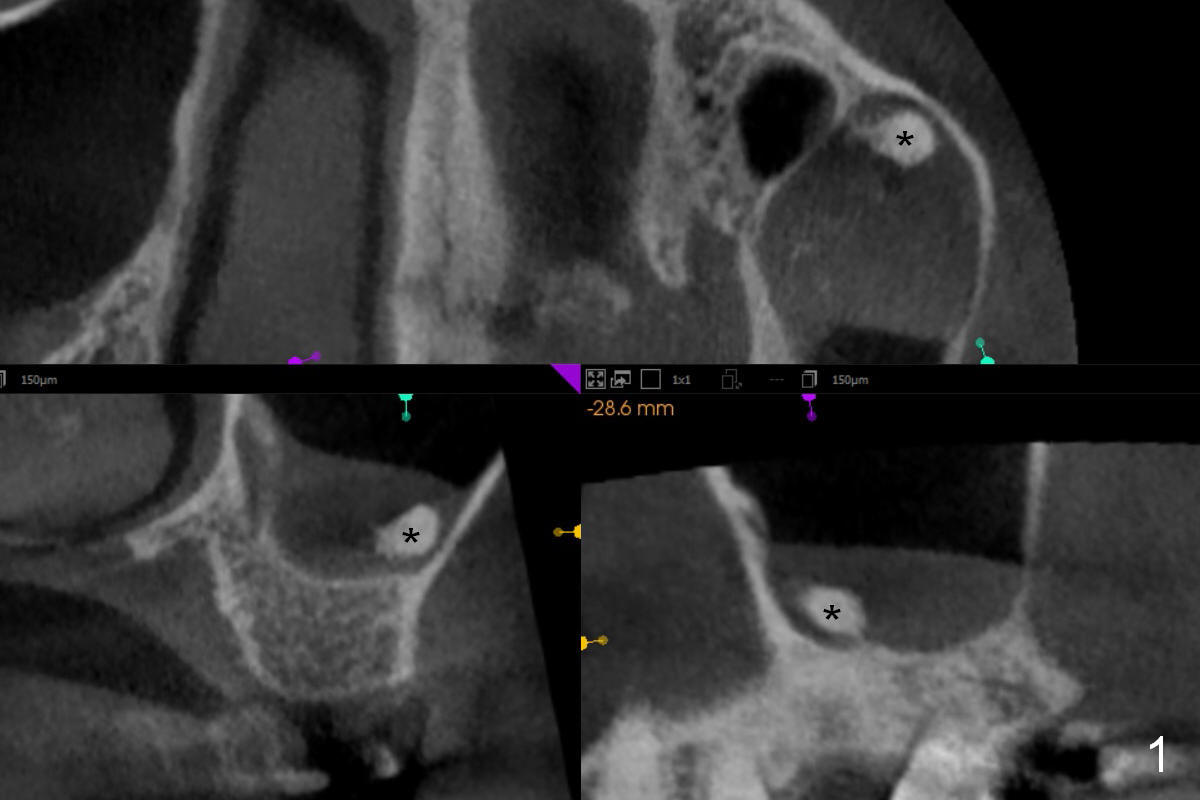

CT shows a residual root in the left maxillary sinus. In order not to re-infect the sinus, an implant at the site of #14 should not enter the sinus (Fig.2) or enters the sinus with bone graft (Fig.3,4 red circles) and more importantly PRF membrane (yellow).

Traditional segmental orthodontic treatment (open coil spring) is to be conducted to increase the mesiodistal width from 4.7 mm to 8 mm to place a 5 mm implant (Fig.2,3). Once the implant osteointegrates, it will be used an anchorage to further distalize the tooth #15.